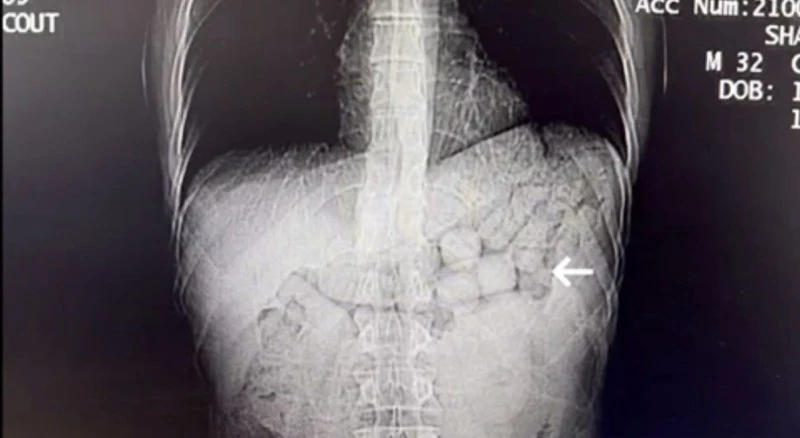

Uyuşturucu Yutma Yöntemiyle Kaçakçılık

Uyuşturucu kaçakçılığının karmaşık ve tehlikeli yöntemleri, güvenlik güçlerini de sürekli olarak yeni stratejiler geliştirmeye zorlıyor. Diyarbakır’daki olayda, şüphelilerin "yutma" yöntemiyle uyuşturucu taşımayı planladığı belirlendi. Şüpheliler, olası bir uyuşturucu yutma şüphesi nedeniyle hastaneye sevk edildi.